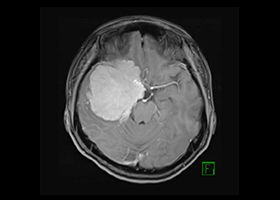

症例1)65歳男性、頭蓋底部巨大髄膜腫、外科手術のみ

[画像所見]

MRI造影検査で巨大脳腫瘍を認めます。